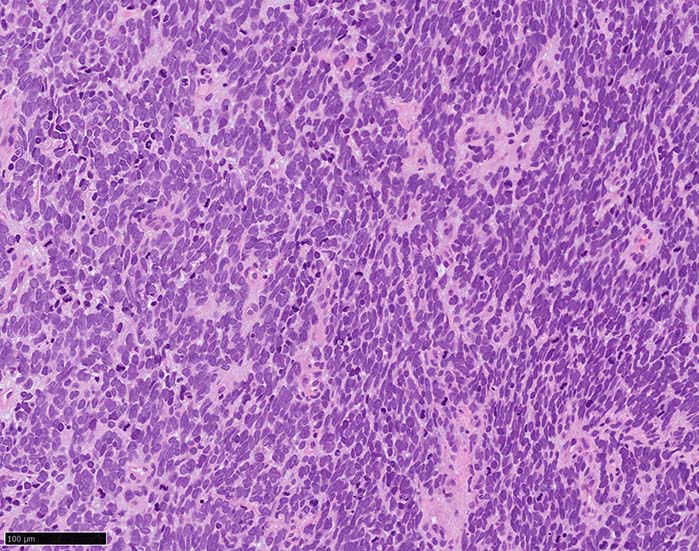

皮膚原発性Merkel細胞癌は 通常真皮を病変首座に増殖し, しばしば脂肪織まで浸潤する.

表皮とは連続性がなくGrenz zoneがみられるのが特徴であるが, 病理所見は多様であり, ときに表皮向性を示す症例やpagetoid patternを呈する症例もある.

典型的な腫瘍細胞は円形, 卵円形の比較的均一な形態で「salt-and-pepper」と称される微細顆粒状クロマチンを有する小型円形核をもつ. MCPyV陽性例が均一な小型円形核を呈する傾向があり, 陰性例では, 核多形性が目立つととする報告がある.

trabecular type, intermediate type, samll cell typeの3パターンの組織型に分類されているがしばしば混在している.

- small cell typeは濃いクロマチン, 多形性を示す核をもつN/C比大の小型腫瘍細胞がびまん性に増殖する.

- intermediate typeではtrabecular, samll cell typeの中間の腫瘍細胞サイズを示す. 組織型としてはもっとも多い.

腫瘍内浸潤リンパ球/炎症細胞は多くの症例で認められる. リンパ球の腫瘍内浸潤は予後良好因子と報告されている. 16

血管を間質にしてround cellsが索状に増殖する所見. rossett様配列がある. CK20は特徴的な dot-like patternを示す. クリックで大きな画像が見られます.